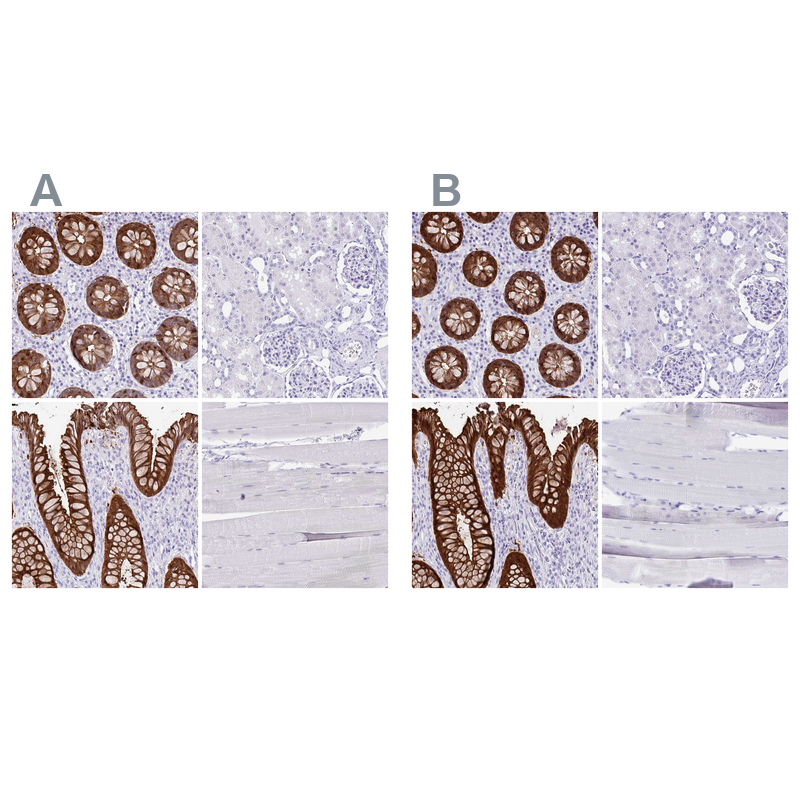

Immunohistochemistry analysis in human colon and cerebral cortex tissues using HPA031185 antibody. Corresponding LGALS4 RNA-seq data are presented for the same tissues.